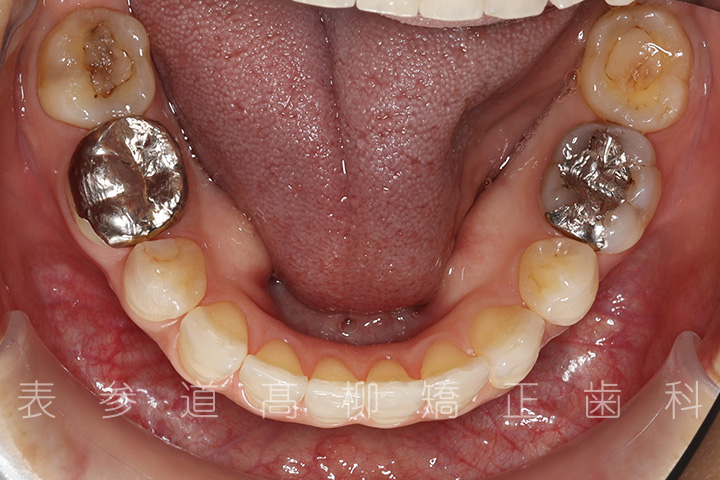

口呼吸と舌癖で前歯が咬み合わない患者様の症例をご紹介いたします。

・前歯部開咬

・上下前歯部叢生(凸凹歯並び)

・口呼吸、舌癖

・上下両側第二小臼歯を抜歯

術前術後の比較